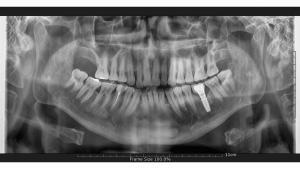

Dies liegt daran, dass es in einigen Fällen eine Infektion in den Zähnen geben kann, die entfernt werden müssen, selbst wenn sie geringfügig ist. Durch die Verwendung von Medikamenten gegen Infektionen stellen wir sicher, dass unsere Patienten einen angenehmeren Implantationsvorgang und eine angenehmere postoperative Phase haben. Wenn unsere Patienten für einen vollständigen Satz von Zahnimplantaten in unsere Klinik in Marmaris, Türkei, kommen, führen wir zunächst eine gründliche Untersuchung mit einem Panorama-Röntgenbild und einer mündlichen Untersuchung durch. Basierend auf den Untersuchungsergebnissen erstellen unsere Ärzte einen Behandlungsplan. Anschließend gehen wir mit dem Implantationsvorgang voran, um unseren Patienten die bestmögliche Behandlung zu bieten.